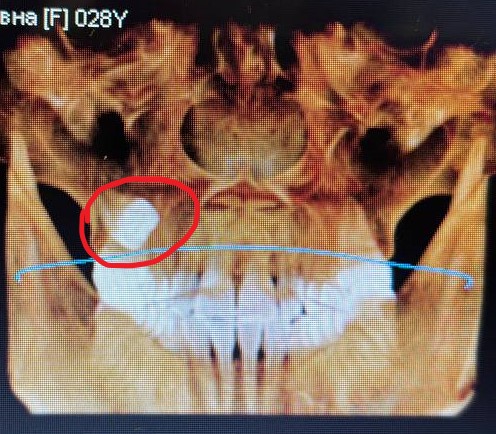

Снимок КТ в клинике делают без расшифровки, а времени для приёма в этот день нет. Сама скачала программу для просмотра и открыла снимок. Обывателю в ней ориентироваться сложно, я смогла только увидеть зуб. Но он не просто зуб, а Гадкий Утёнок в мире стоматологии: лежит боком, в саааамой глубине челюсти, и выглядит так, будто его удалять будут вместе с половиной моей головы. Запись к хирургу — на следующее утро.

Хирург №1 смотрит на десну — воспаление. Смотрит на снимок КТ — охает. Делает рентген — ахает. Зуба на рентген-снимке не видно вообще. Вердикт: «Слишком сложно, слишком далеко и глубоко лежит, мы не удалим. Езжайте в челюстно-лицевую хирургию областной больницы».

Кабинет хирурга №2. Врач изучает десну, загружает мой злополучный снимок КТ в программу, покручивает его какое-то время… и произносит фразу, достойную кульминации триллера:

— А вы в курсе, что этот жуткий зуб у вас… с левой стороны?

— Справа у вас банальный кариес, — продолжает врач спокойно и показывает проблемное место на снимке. — Лечится без проблем у терапевта. А этот «монстр» слева пусть себе спит, пока не беспокоит. Трогать сейчас его не надо.

Но если бы первый хирург не испугался сложного зуба и взялся за удаление… он бы просто вскрыл мне здоровую десну (наживую, ага) не с той стороны. Только потому, что не разобрался как следует в снимке. Потому что не повернул проекцию. Потому что не поставил галочку в программе.